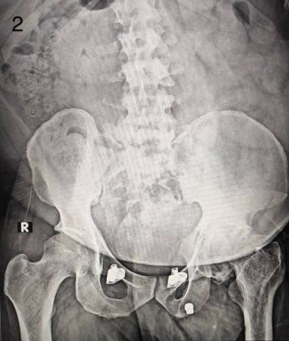

Interestingly, AVN of the hip was more frequently observed on the right side (50%) compared to the left (41.67%) and bilateral presentation (8.33%) among patients with a history of COVID-19. Figures 1 and 2 describe Plain X-rays of pelvis with both hip joints of a 51 year old male and a 43 year old male, having stage 4 AVN of hip, involving the right and left sides respectively. Figures 3 and 4 represent the post-operative X-rays of the above mentioned patients after uncemented THR on the respective sides.

Figure 2: Plain X-ray of pelvis with both hip joints of a 43 year old male having stage 4 AVN of hip, involving the left side.

Figure 2